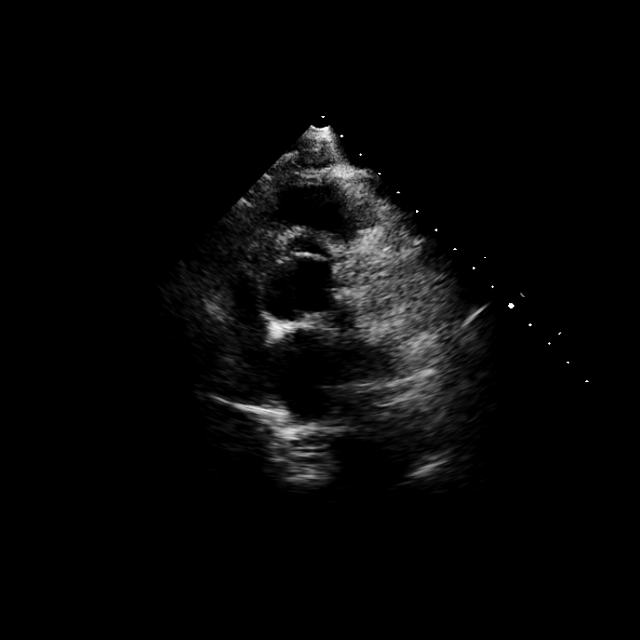

We assess the quality of visual representations by finetuning each VLM’s vision encoder on a private, multi-vendor TTE dataset collected from six sites (26k videos with 18 ASE-standard views, including contrast). All data are de-identified and converted to grayscale. The dataset is split into 21.5k/2.1k/2.1k videos for training, validation, and testing, respectively. A linear classification head is attached to the pooled visual embeddings, and the encoder is fine-tuned end-to-end (details in Appendix Table 10).

EchoVLM achieves state-of-the-art performance in view classification.

EchoVLM achieves the best performance among all evaluated models (Table 2), reaching 95.1% accuracy, 95.3% F1 score, and 95.8% precision. Notably, EchoVLM not only surpasses all VLM baselines but also outperforms the strongest vision foundation model EchoApex by 0.9% in precision. We also provide class-wise analysis in Figure 11. EchoVLM consistently achieves higher balanced accuracy than EchoCLIP across most ASE-standard views, with improvements that are statistically significant for the majority of classes (, one-sided -test). These results highlight that our pretraining strategy yields transferable and clinically meaningful visual features, extending beyond multi-modal alignment to purely vision-based tasks.111As EchoPrime is a video-based model, the results are evaluated based on using 16 consective frames rather than single image from the echo video.